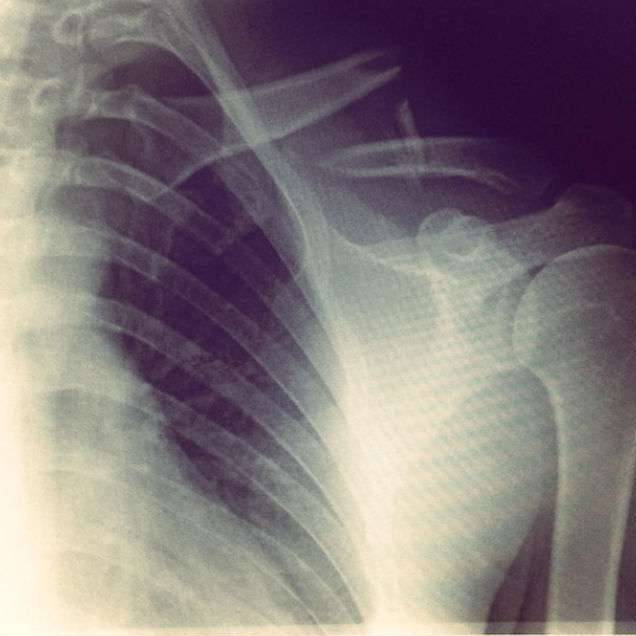

▼这次摔倒导致他4根肋骨和锁骨骨折,情况很严重。

▼医生用金属板将他的锁骨固定起来,从那之后,他又接受了一年多的治疗,这才完全康复。